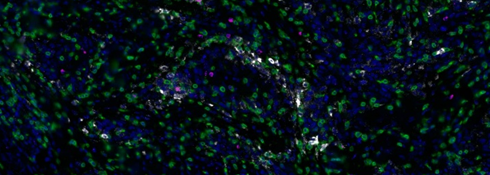

자궁경부암 조직에서 세포독성 T 세포를 분석하기 위해 T 세포는 단백질 마커 CD3로 식별하였으며 cytokine 마커 IFNG와 CXCL9은 RNA 신호로 검출하였습니다.